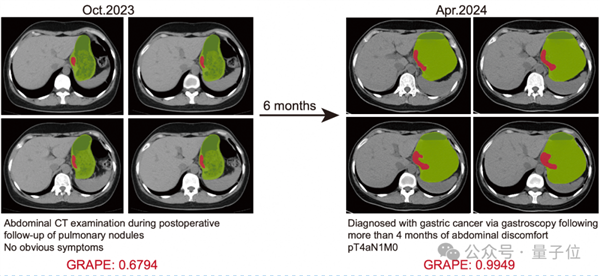

论文共同一作、浙江省肿瘤医院胃外科博士胡灿提到,2024年4月,一名患者检测出局部晚期胃癌。医生对其进行回溯研究时,将其6个月前检查其他疾病做过的平扫CT影像喂给DAMO GRAPE,就提示其存在早期胃癌病灶。

假使当时就有AI自动检测,这名患者将提前6个月确诊并接受治疗。

△AI提前6个月识别出胃癌

这并非个例,在此次研究中,共回顾了11名患者确诊前的CT影像,发现AI可提前2到10个月不等检测出胃癌。